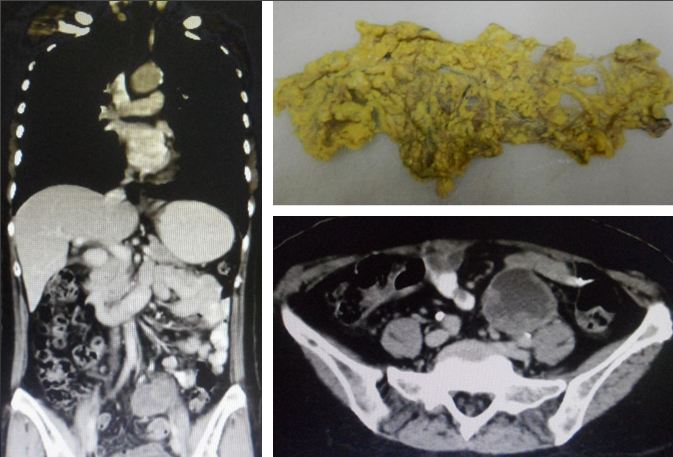

A CT scan was done and there was a 9 cm cyst in her peritoneal cavity. Eka underwent another operation to remove the cyst. The histopathology report confirmed a high grade peritoneal serous carcinoma — left pelvic cyst wall. This operation cost her RM30,000.